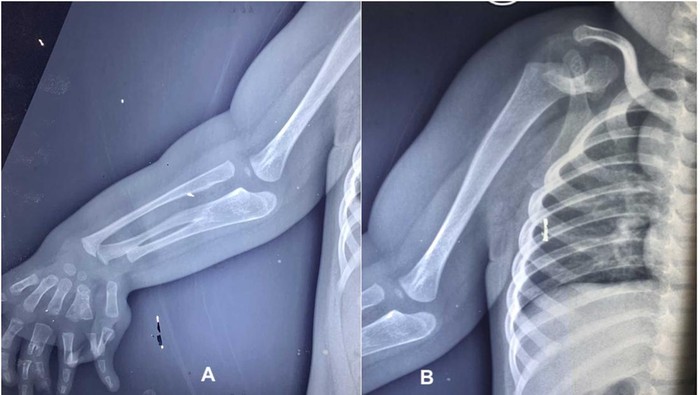

Seorang anak laki-laki berusia dua tahun di India, terlahir dengan kondisi langka anomali kongenital (congenital anomalies) yang membuat dirinya mengalami tiga lengan bawah dan duplikasi jari. Kasusnya ini diterbitkan dalam jurnal PlumX Metrics pada 2024, dengan judul ‘Congenital three-bone forearm – A rare disorder’.

Berdasarkan hasil pemeriksaan, terlihat adanya pengecilan otot yang nyata di sekitar bahu dan skapula, disertai tidak adanya gerakan aktif pada abduksi, fleksi, maupun rotasi bahu. Siku dalam posisi fleksi 30 derajat tanpa kemampuan melakukan supinasi maupun pronasi. Lengan bawah dan pergelangan tangan tampak melebar.